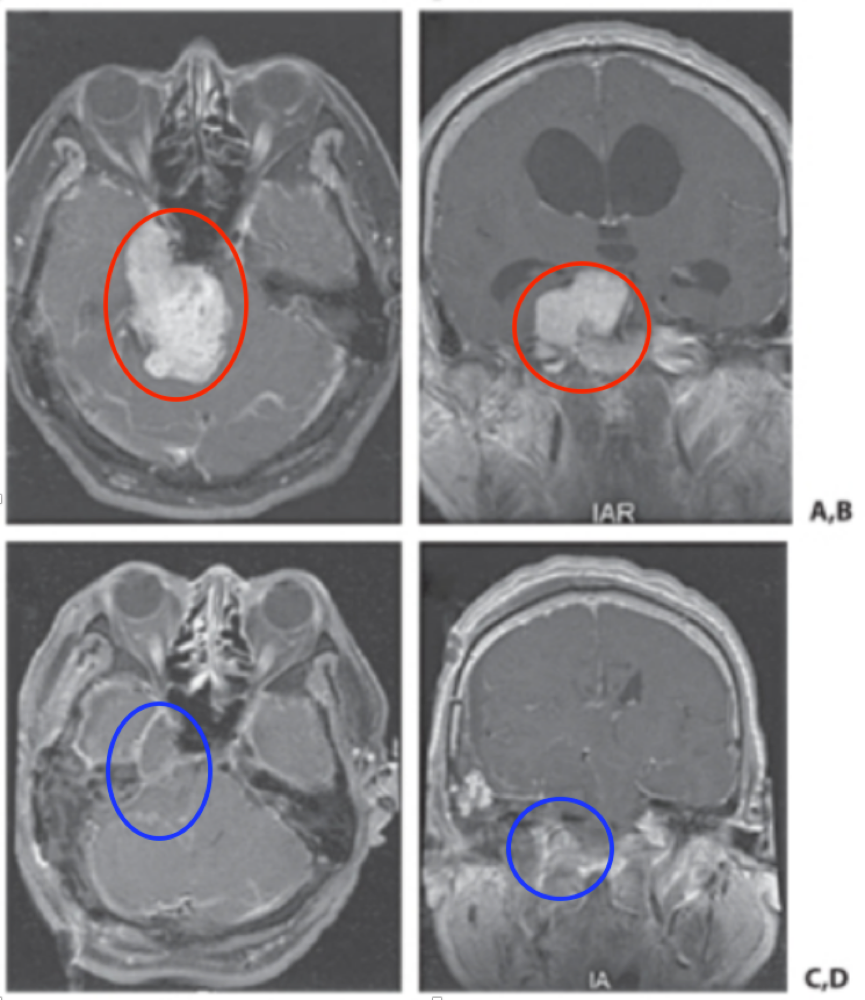

术前评估显示一名54岁男性患者因进行性行走不稳症状及突发性眩晕就诊,影像学检查发现脑干旁巨大三叉神经鞘瘤,术前MRI呈现典型"哑铃型"形态。由于肿瘤压迫脑干且跨越前、中颅窝,手术易导致神经损伤或肿瘤残留,治疗难度较大。经多家医院评估均认为治疗难度较高,最终由William T. Couldwell教授团队采用岩骨联合入路成功实现肿瘤全切,术后MRI证实完全切除。

图A、B显示术前MRI可见巨大三叉神经鞘瘤伴脑干受压,图C、D为术后MRI显示肿瘤完全切除。患者术后未出现手术相关副作用,无明显并发症,三年随访未见复发。